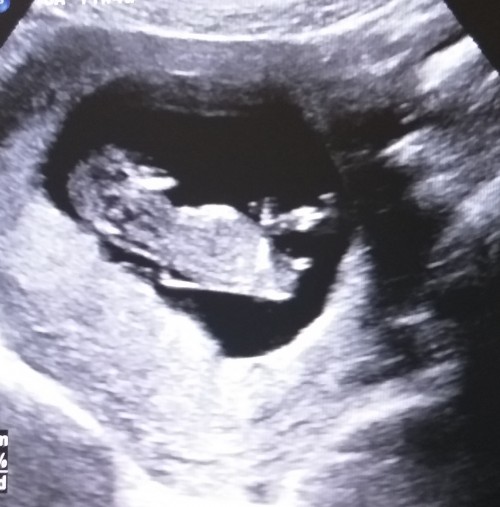

KIZLAR nub teorisine  gore cinsiyet nedir çok merak ediyorum 12+2  günlüğüz  doktorumuz erken cinsiyet için diyor :((

Ama daha çok erken ne kadar merak etsende bence net görünmesi daha mantıklı ben içim içimi yedi yinede 17 haftaya kadar bekledim öyle baktım. Tahmini. Erkeğe benziyor pek anlamam ama erkek olabilir

Canım nuba göre erkek görünüyor doğrusunu doktorun söyler zaten.

Bilmiyorum kizmidir ama Ben erkeğe benzettim.

nuba gore kiz kesin dr